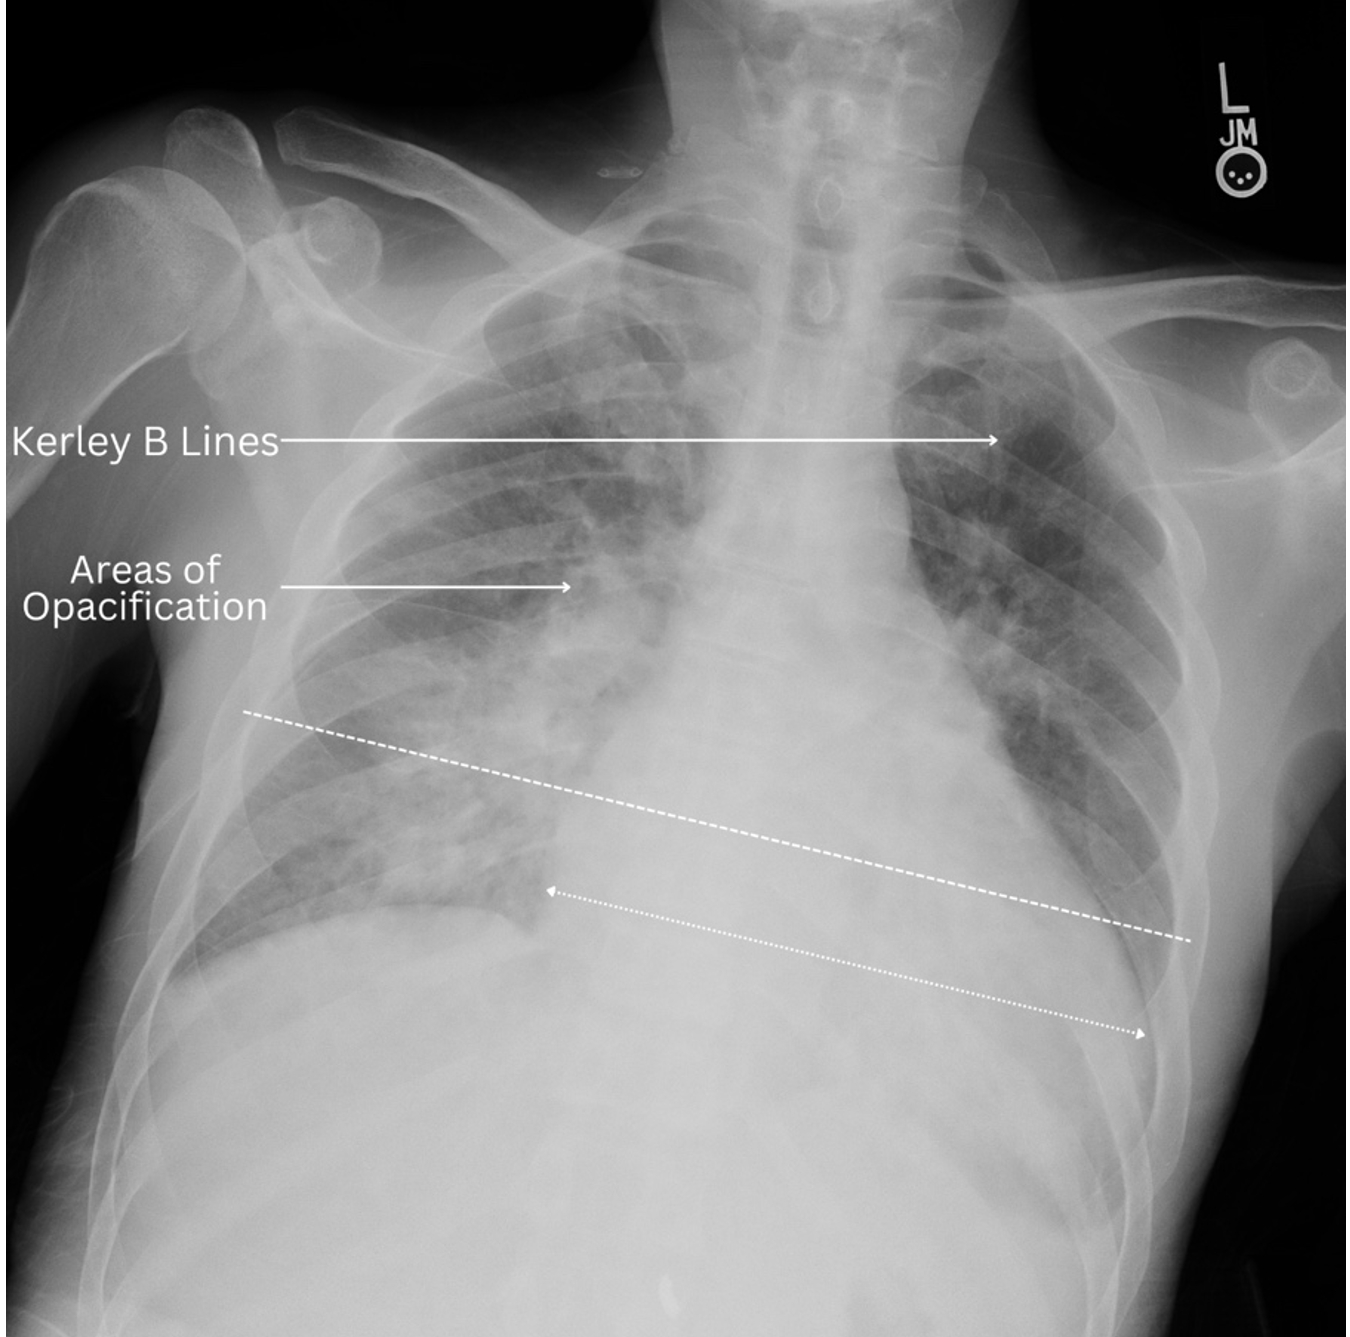

A 47-year-old male with supposed history of rheumatoid arthritis (RA) presented with shortness of breath and had a cardiac arrest in the ED. He was found to have an ejection fraction of 10-15%. Ischemic evaluation and genetic testing were negative. Dermatologic findings of the Gottron sign, heliotrope rash, shawl sign, and mechanic’s hands were noted along with crackles in his lungs. Inflammatory markers were elevated but creatine kinase (CK) and aldolase were normal. Rheumatoid factor, anti-CCP, and anti-Jo-1 antibodies were negative. Myositis panel revealed high positive MDA-5 antibodies. Lung biopsy revealed ILD and endomyocardial biopsy showed evidence of inflammation. He was treated with steroids and intravenous immunoglobulin with inotropic support.

Anti-MDA5 dermatomyositis is known to be associated with high mortality related to rapidly progressive ILD. In contrast, this patient’s course was dominated by myocardial disease. Cardiac involvement in clinically apparent in only 10-20% of patients, and myocardial inflammation can lead to complications with poor outcomes. Furthermore, the lack of classic weakness and normal CK and aldolase posed a diagnostic challenge. Early diagnosis and initiation of anti-inflammatory therapy is essential to mitigate the high mortality rates associated with this elusive disease.